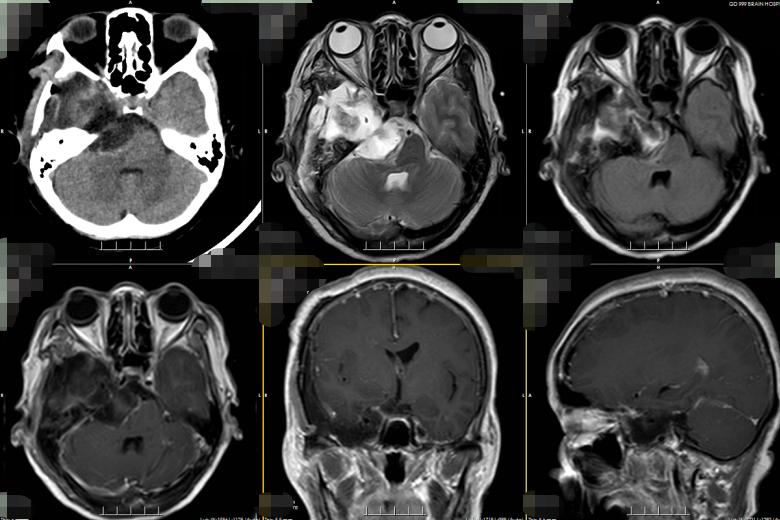

经过多次讨论分析,吴杰团队最终决定采用颞下入路,实施右侧岩斜区跨中后颅窝占位性病变切除术。术中可见质地硬韧的黄褐色肿瘤侵犯海绵窦、压迫脑干。吴杰小心翼翼分离肿瘤与周围神经,在显微镜下全切肿瘤,未伤及周围血管神经!

术后病理诊断为神经鞘瘤,证实吴杰术前的诊断。术后,群姐恢复得良好,症状也都消失,很快便出院了。

▲术后复查